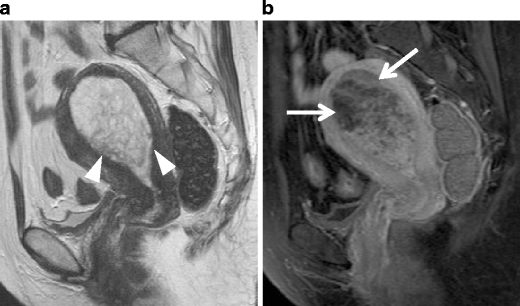

Endometrioid carcinoma in 53-year-old woman. a Sagittal T2-weighted image demonstrates an ill-defined endometrial tumor. The endometrial-myometrial border is almost entirely obscured, suggesting the myometrial invasion by the tumor. b Early-phase image of dynamic enhanced T1-weighted clearly demonstrates inner myometrium of strong enhancement (arrowheads), which become irregular by invading tumor

Serous carcinoma in a 55-year-old female. a Sagittal T2-weighted image demonstrates an endometrial tumor of decreased intensity occupying the endometrial cavity, and protruding into the external cervical os. Note the endometrial-myometrial border in both the corpus and cervix is diffusely obscured, suggesting myometrial invasion of the tumor (arrowheads). There is a small implant on the posterior serosal surface of the uterus (arrow). b Fusion image of DWI onto T2-weighted image exhibits increased intensity corresponding to the tumor in the endometrial cavity. The implantation on the posterior wall is also clearly demonstrated with excellent tissue contrast (arrowhead)